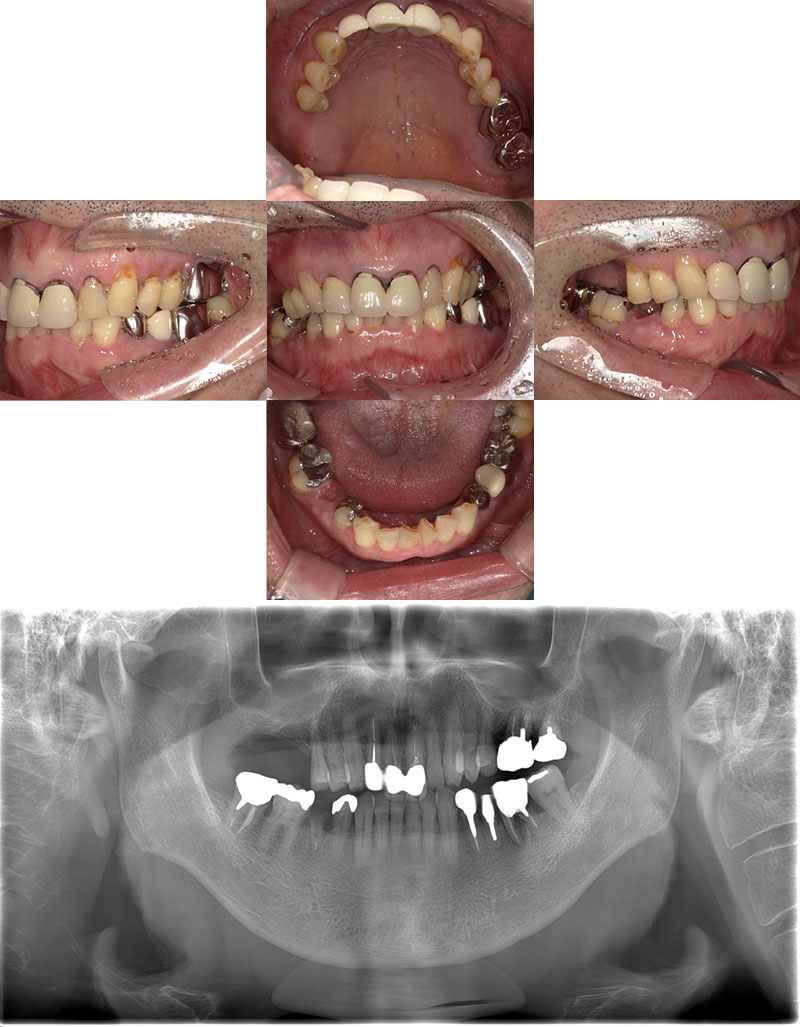

インプラント+矯正+メタルフリー症例

治療前

Before

治療後

After

年齢 38

性別 男性

主訴 全体的に歯を綺麗にしたい